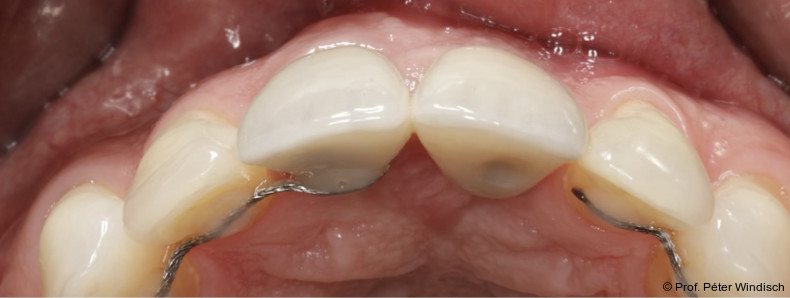

Radiologisch war ein signifikanter Knochenabbau um das Implantat zu verzeichnen (Abb. 2). Die klinische Untersuchung zeigte klassische Anzeichen einer periimplantären Entzündung: Bluten auf Sondieren (BOP+), erhöhte Sondierungstiefen (ST) und eine lokale Schwellung der Mukosa (Abb. 3–5). Das primäre Ziel war es, den Entzündungsprozess nicht chirurgisch zu stoppen und ein biologisches Milieu zu schaffen, das eine langfristige Stabilität ermöglicht. Der Implantataufbau wurde derzeit am Halsbereich zu dick ausgearbeitet und wies aus diesem Grund kein optimales Emergenzprofil auf. Nach der Eingliederung der definitiven prothetischen Versorgung kann es – insbesondere bei dicken suprakrestalen Weichgeweben – vorkommen, dass sich das Weichgewebe an die Kronenkontur adaptiert, was biologisch nicht immer gut toleriert wird. In der Folge kann es zu einer lokalen entzündlichen Reaktion kommen. Aus diesem Grund war zudem eine Umgestaltung der Krone vorgesehen.

Das Emergenzprofil wurde mit einer polierten, eindeutig konvexen „S-Kurve“ neu gestaltet (Abb. 9+10). Diese neu entwickelte Geometrie schafft ausreichend Raum für die Weichgeweberegeneration, stützt den Gingivasaum, ohne durch überkonturierte („bulky“) Formen Nischen für Plaque zu schaffen. Die Synergie aus einer biokompatiblen Materialoberfläche (polierte Keramik) und einer reinigungsfähigen Anatomie stellt sicher, dass die Ergebnisse der submarginalen Instrumentierung dauerhaft stabil bleiben und der Patient die Stelle effektiv mit Interdentalbürsten pflegen kann.